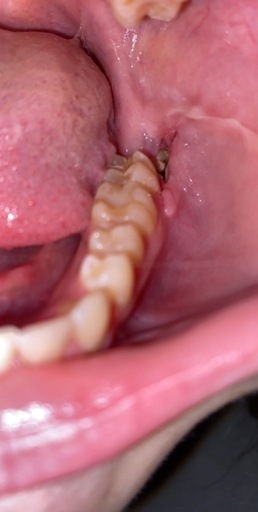

Jaw Bone Showing After Wisdom Tooth Extraction

Hello! One week ago I have two wisdom teeth removed, both being on the same side of my mouth. I had an infection on my bottom wisdom tooth and was given antibiotics prior to the extraction. Since the surgery, I have had dull pain from that one side of my face and most of it coming from my lower jaw. I looked in the mirror and noticed that next to my extraction site, there was my jaw bone showing with a very small hole above it. Now, there are days where I need very little pain meds to deal with it (200mg Advil, for example), but I had a few times where it was just hurt really bad. It is always aching. I have being rising with salt water and peroxide and always after meals but I have noticed that the salt water irritates it. Before I see my dentist, I was wondering what could it be? Is this a new infection? Is this something that will heal on its own, such as my gum tissue covering my jaw bone back up? Thank you!